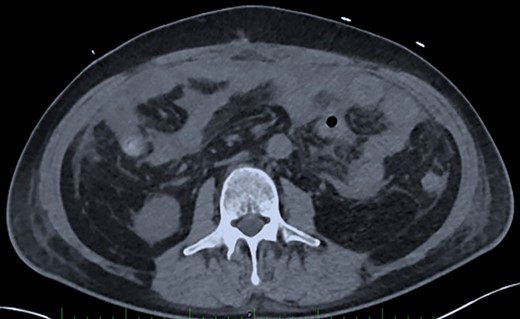

Post-operative Day 14. Abdominal CT-scan with free intraperitoneal fluid, without sign of ileus, perforation or anastomosis release.

Renal replacement therapy was required until Day 10, mechanical ventilation and catecholamines support until Day 12. On Days 13 and 14, the patient did not present any fever or abdominal pain, CRP levels were at 125 mg/l and 196 mg/l, respectively and white blood cell (WBC) counts were stable at 20 G/L. Blood levels of PSP were determined to be 387 ng/ml on Day 14, measured on the point-of-care abioSCOPE® device (Abionic SA, Epalinges, Vaud, Switzerland). This high concentration of PSP (>290 ng/ml [4]) triggered an abdominal CT-scan which showed free fluid, no sign of ileus, perforation or anastomosis release (Fig. 2). Despite this result and absence of clinical signs, the patient was rescheduled for surgery based on the high PSP value. The laparotomy revealed a loosening of the ileal anastomosis and confirmed the presence of a diffuse post-operative peritonitis. A second distal ileostomy was performed along with abundant peritoneal lavage, abdominal wall VAC. Escherichia coli, Enterococcus faecalis and S. aureus were detected in the peritoneal fluid cultures 48 h later, and antibiotic therapy with imipenem/cilastine/fluconazole was maintained. From Day 14 onwards, PSP, CRP and WBC were dosed daily. These three biomarkers progressively decreased to reach values of 225 ng/ml, 157 mg/l and 12.3 G/L, respectively on Day 18.